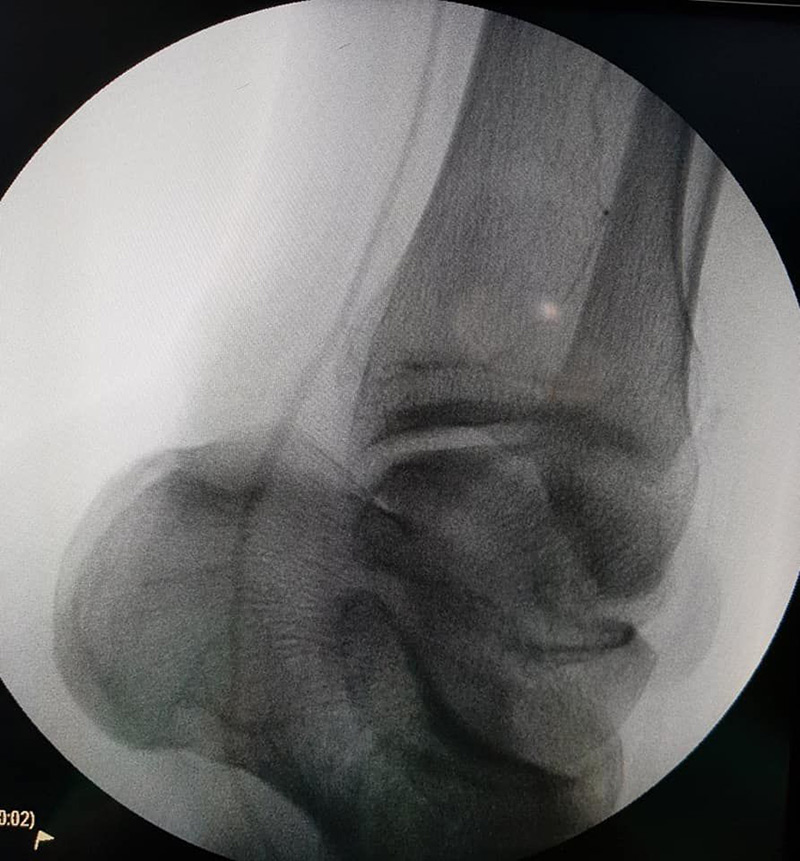

วันที่ 21 มกราคม 2564 ผู้สื่อข่าวรายงานว่า แพทย์รายหนึ่งของโรงพยาบาลหาดใหญ่ จ.สงขลา ได้โพสต์เฟซบุ๊ก Jirat Jiratham-opas เกี่ยวกับเหตุการณ์อุทาหรณ์ที่เกิดขึ้นกับชายหนุ่มคนหนึ่ง ที่เข้ามารักษาอาการปวดขา 2 ข้าง ที่เป็นมานาน 2 วัน โดยเท้าข้างขวาชา ขยับนิ้วเท้าไม่ได้ เท้าข้างซ้ายแค่ชา จึงได้ตรวจอาการโดยการทำ CTA เส้นเลือดที่ไปเลี้ยงขาดับทั้ง 2 ข้าง

หลังทราบผลการตรวจแพทย์แนะนำให้รีบผ่าตัดด่วน ไม่อย่างนั้นจะเสียขาทั้ง 2 ข้าง แต่ผู้ป่วยหนุ่มคนนี้กลับไม่ยอมผ่าตัด พร้อมบอกว่าขอเวลาทำใจกลับบ้าน โดยแพทย์ได้พยายามอธิบายหลายรอบ และบอกอนาคตที่ชัดเจนหากยังไม่รีบรักษา แต่ชายคนนี้ก็ยังคงไม่ยอมผ่าตัด แพทย์จึงขอต่อรองให้นอน รพ. เพื่อให้ยาละลายลิ่มเลือด แต่ผู้ป่วยคนนี้กลับอาละวาด และพยายามทำร้ายเจ้าหน้าที่

และหลังจากนั้นอีก 1 วัน คนไข้คนเดิมก็ได้กลับมาอีกครั้ง เพราะปวดจนทนไม่ไหว แต่รอบนี้อาการหนักกว่าเดิม เท้าดำไปหนึ่งข้าง พร้อมยกมือไหว้ขอให้ช่วย แต่อาการล่าสุดพบว่า เนื้อขาขวาตายและมีสีดำแล้วต้องตัด ส่วนขาซ้ายก็อาการหนัก ทางแพทย์จึงระดมเจ้าหน้าที่ช่วยกันอย่างเต็มที่ โดยใช้เวลาในการผ่าตัดนานกว่า 8 ชั่วโมง จนสามารถรักษาขาซ้ายเอาไว้ได้ ไม่ต้องถูกตัดขาทั้ง 2 ข้าง